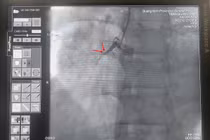

Kỹ thuật Mini Crush là tái thông lòng mạch bị hẹp ở cả hai nhánh chính và phụ được tối ưu, giúp giảm triệu chứng đau ngực và suy tim ở bệnh nhân có tổn thương vị trí chia đôi của động mạch vành.